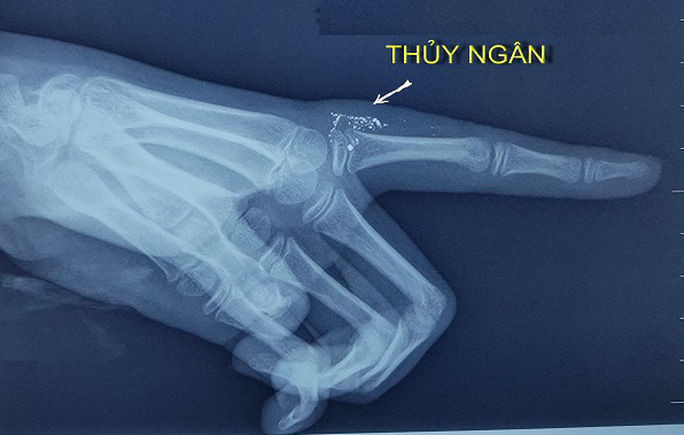

Hạt thủy ngân trong tay qua hình ảnh phim X-quang - Ảnh: Bác sĩ cung cấp

Khi vào viện, vết thương của cháu bé đã bị nhiễm trùng và áp xe. Các bác sĩ chụp X-quang ngón tay của cháu thấy có nhiều hạt thủy ngân ở bên trong phần mềm sát khớp bàn ngón trỏ tay trái. Do tình trạng nhiễm trùng phức tạp, cháu đã được điều trị nhiễm trùng, xét nghiệm nồng độ thủy ngân trong máu, nước tiểu và đánh giá các tổn thương.

Hiện vết thương của bệnh nhi đã ổn định. Các bác sĩ đã chụp cắt lớp, siêu âm để đánh giá kỹ số lượng hạt thủy ngân và vị trí chính xác ở ngón tay để chuẩn bị cho cuộc mổ loại bỏ các hạt thủy ngân. Dự tính dù vị trí phẫu thuật nhỏ nhưng cuộc mổ đặc biệt do cần phải lấy hết các hạt thủy ngân một cách an toàn.